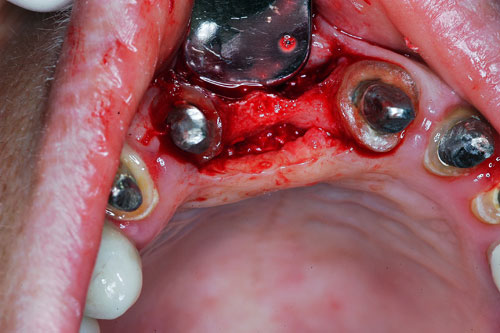

Mientras dichos movimientos ortopédicos se producen (período que supondrá otros seis meses), estudiamos los actos quirúrgicos a realizar en los cuatro implantes que pondremos. De acuerdo al estudio Desatascan realizado observamos tres situaciones diferentes: 1º-El Primer Molar Inferior Izquierdo, lo instalamos mediante Cirugía Minimamente Invasiva , con la aplicación de una Férula Quirúrgica Obtenida de los datos del scanner tratados con un programa de CMI (Cirugía Minimamente Invasiva), previa prueba en un modelo estereolitográfico, ya que la altura ósea era apenas de 9 mm. 2º- El Primer Molar Superior Derecho, se implantará mediante una ligera Elevación Atraumática (Trans alveolar) de Seno una vez logrado el espacio mesio distal necesario. 3º- El Incisivo Central Superior Derecho ausente, cuenta con un sustrato óseo prácticamente inexistente. El espesor de la tabla era de menos de 2 mm. Los caminos posibles a seguir para contar con una Rehabilitación de piezas independientes son dos: Optamos por esta segunda opción por ser menos cruenta y no necesitar de una zona dadora. Técnica esta que pondremos en práctica en dos etapas diferidas: 1º-Incisión horizontal palatinizada, incisiones peri rodetes gingivales e incisiones de descarga. Dilatación que comenzamos con dos incisiones de descarga sobre la cortical vestibular realizadas con disco. y el comienzo de la dilatación propiamente dicha mediante una hoja de bisturí, para luego seguir con un periostótomo . Recién después de alcanzada una cierta separación de la cortical vestibular de la palatina, empezamos con los dilatadores roscados. En este punto podríamos haber utilizado sin riesgos un Implante de 3,8 mm de diámetro, pero a fin de mejorar la estética del pilar emergente decidimos rellenar con material osteoconductor y osteoinductor (BiOss) y cubrir mediante membrana reabsorvible ( Bio Guide). 2º-Implantación seis meses después. Mientras se van cumpliendo los tiempos antes mencionados, y comprobamos reiteradamente la funcionalidad de la oclusión con los provisorios, tomamos impresiones definitivas y construimos primero el maxilar inferior, para definir en primer término la porción inferior de la Guía Anterior., y a nivel posterior Curvas y Microplanos. Para luego realizar los cuadrantes premolar- molar del superior: La espera de la regeneración ósea y sus tiempos pertinentes, más la espera de los tiempos de la implantación, nos obligaron a modificar las etapas del protocolo D.AT.O de manera de mantener la –D- mediante el sector superior de la GA. en provisorios, mientras fuimos resolviendo en forma definitiva los demás sectores. Ya pasados los meses necesarios para recrear un hueso adecuado en el área del Incisivo Superior Derecho, procedemos a resolver la implantación de dicha zona, observando que todo el esfuerzo dedicado al mismo había sido inútil, ya que la formación de hueso se produjo minimamente. Cuatro meses después tomamos impresiones del sector Antero Superior de la Guía Anterior, incluyendo el arrastre de un transfer . Seguimos modelando la encía con un nuevo juego de provisorios. Y se construye entonces el sector superior de la Guía Anterior. Se efectúa un control radiográfico a los 6 meses. Se ha intentado mostrar en esta Rehabilitación, que a pesar de las distintas circunstancias de cada paciente, siempre debemos tener en cuenta la necesidad de ejercer la DESOCLUSIÓN del caso como prioridad número uno, para luego perseguir la ALINEACIÓN TRIDIMENSIONAL de las arcadas y obtener así una OCLUSIÓN equilibrada. D.AT.O. ES EL PROTOCOLO QUE DEBEMOS SEGUIR EN TODA REHABILITACIÓN. BIBLIOGRAFÍA 1)William Mc Horris,B.S.,D.D.S. Oclusión. Con especial énfasis sobre :El rol funcional y parafuncional de los dientes anteriores. 2)Von Spee , Craff(Anatomista alemán, describió la curva de compensación de la articulación de molares y premolares).CURVA DE SPEE 1.89 3)Stuart,D.”Some aspects of the inervation teeth.”Procedings of Royal Society of Medicine.20:1675,19274)Muhleman,H. y Savdir,S”Tooth movility-its causes and significance”Journal of Periodontology ,36:153,Marzo ,Abril,1965. 4)Muhleman,H. Y Savdir,S”Toothmovility its causes and significance” Journal of Periodontology,36:153,marzo,abril,1965. 5-Oclusión y Diagnóstico en Rehabilitación Oral. 6-Anatomia Odontológica. 7-A contribution to the study of the movementes of the mandible. 8-Celenza F.W, Nadeskin J.F.,Oclusión.Situación actual. 9-D´Amico 10-Dawson P.E. 11-Huffman –Regenos. 12-Hobo S.-Takayama H.A. 13-Lucia V.O 14-Mc Horris. 15-Mc Horris. 16-Stuart C. 17-Vartan Veshnilian 18-Alvarez Cantoni H. AUTOR:Ratificación del Protocolo en Rehabilitación Bucal a pesar de las incidencias propias de cada caso clínico. A propósito de un caso.

Tridimencionalización mediante implatemetric y ensayo de colocación de implantes

Tridimencionalización mediante implatemetric y ensayo de colocación de implantes

Verificamos también el escaso ancho crestal, lo que nos obliga a utilizar dilatadores roscados y un osteótomo para elevar inicialmente la membrana de Schneider.

Elevación de membrana mediante periostótomo

Elevación de membrana mediante periostótomo